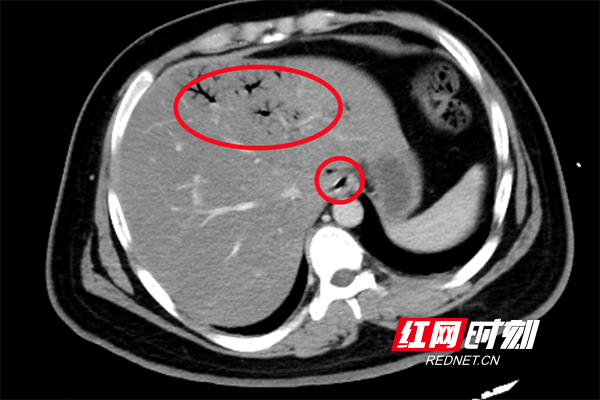

【小伙长期喝饮料吃外卖住进EICU】近日,湖南长沙,从事IT行业,仅仅21岁的小刘,与家人视频时昏迷。送医后,经检查,小刘血糖超出正常值20多倍、小肠坏死,被送入EICU抢救治疗。